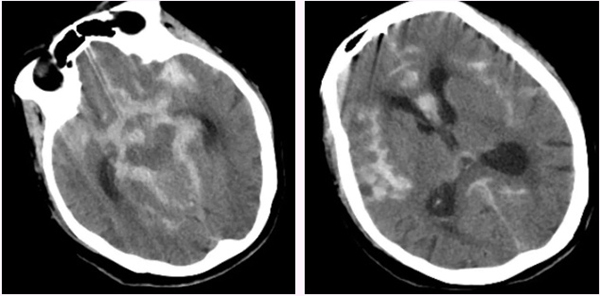

赵女士今年已85岁高龄,患高血压病已30余年,冠心病10余年,曾置入5枚冠状动脉支架,平时可自理。7月8日晚间在家中洗澡时突发剧烈头痛,伴恶心呕吐,紧急来到北京市垂杨柳医院急诊内科就诊。经为患者行头颅CT检查提示蛛网膜下腔出血,急诊当即请神经外科会诊。神经外科值班医生刘耀东赶到急诊,查看患者呈嗜睡状态,颈项强直。紧急为患者安排了头颈动脉CTA检查,显示前交通动脉瘤。

▲头颅CT显示广泛蛛网膜下腔出血,脑室积血